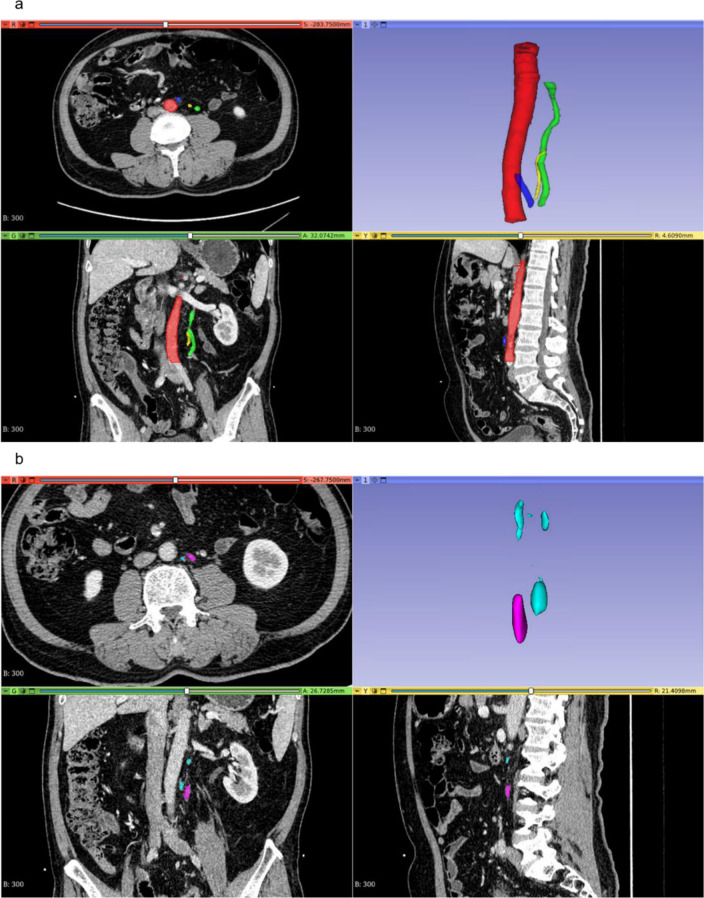

Methods: We retrospectively collected clinical data from 2,118 patients with left-sided CRC and contrast-enhanced CT images from 310 of these patients. From this data, a test set, a training set, and a temporal validation set were constructed. Logistic regression models were used to develop a clinical model, a CT model, and a radiomics model, which were then integrated into a combined model using logical rules. Finally, these models were evaluated using metrics such as the area under the receiver operating characteristic curve (AUC), precision-recall (PR) curves, decision curve analysis (DCA), net reclassification improvement (NRI), and integrated discrimination improvement (IDI).

Results: A clinical model, a CT model, and a radiomics model were constructed using univariate logistic regression. A combined model was developed by integrating the clinical, CT, and radiomics models, with positivity defined as all three models being positive at a 90% sensitivity threshold. The clinical model included six predictive factors: tumor site, endoscopic obstruction, CEA levels, growth type, differentiation grade, and pathological classification. The CT model utilized largest lymph node average CT value, short-axis diameter and long-axis diameter. The radiomics model incorporated maximum gray level intensity within the region of interest, large area high gray level emphasis, small area high gray level emphasis and surface area to volume ratio. In the test set, the AUCs for the clinical, CT, radiomics, and combined models were 0.694, 0.663, 0.72, and 0.663, respectively, while in the temporal validation set, they were 0.743, 0.629, 0.716, and 0.8. Specifically, the combined model demonstrated a sensitivity of 0.8 and a specificity of 0.8 in the temporal validation set. By comparing the PR and DCA curves, the combined model demonstrated better performance. Additionally, the combined model showed moderate improvements in INR and IDI compared to other models.